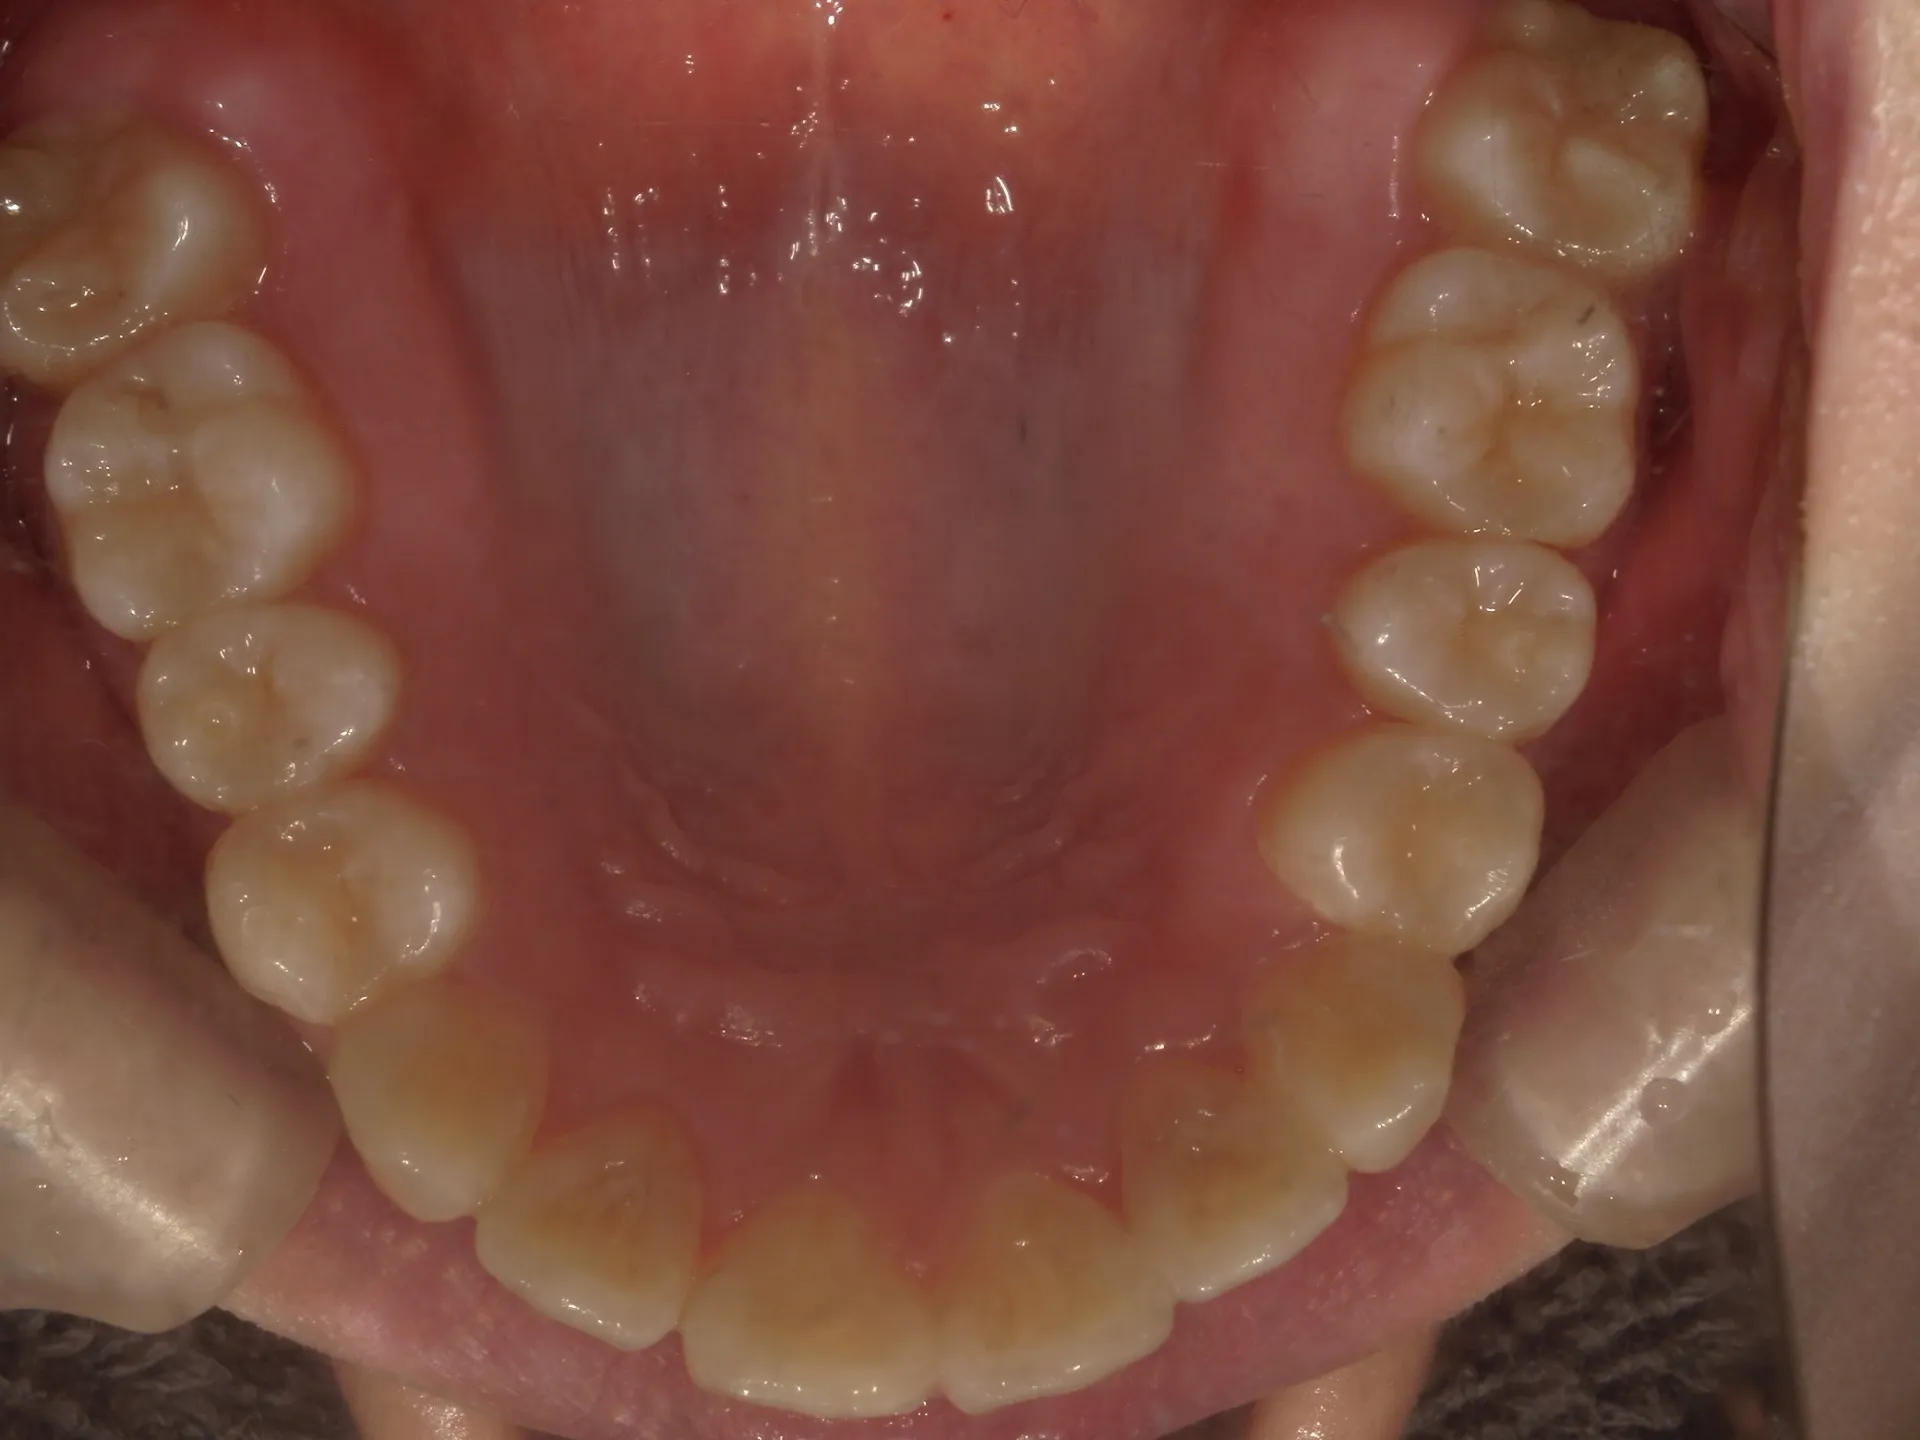

今回はマウスピース矯正で治療した八重歯の矯正についてご紹介いたします。

どこまでが軽度でどこまでが中等度のガタツキなのかにもよりますが、治療前の歯並びであれば患者さんの協力も当然必要ですが、マウスピース矯正でも十分治療できることが分かります。